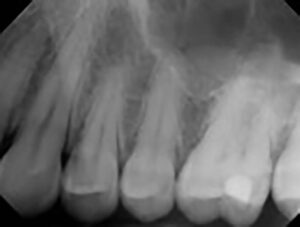

Periapical X-rays:

Periapical X-rays provide a comprehensive view of individual teeth, from the crown to the root tip. These X-rays are invaluable for identifying issues such as abscesses, cysts, and root canal abnormalities, enabling prompt intervention and treatment.